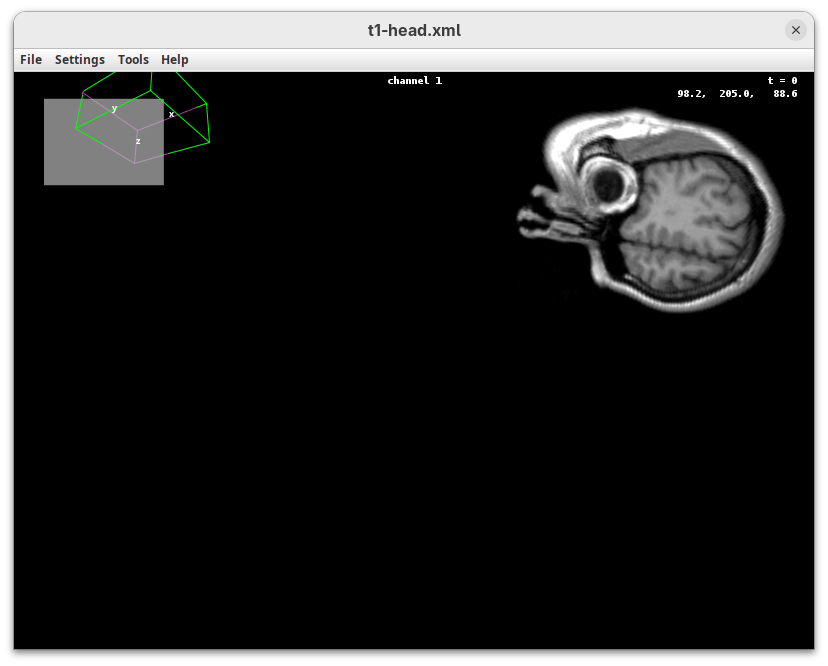

The transformation menu has controls for rotating, translating, and scaling the sample. We can either add values or manually interact with the 3D Animation window to reorient the sample. Let’s try the latter.

- Left-click on the head and move it around.

That’s a great way to see your sample from different angles. And note that the values in the Transformation panel get updated every time you move the sample interactively. In this way you can roughly position the sample and then check and update the precise values for the target transformation.

- Press

Resetand change theRotation Yto180to look at the right side of the head.

- Now change

Scaleto5andTranslation Xto-500to focus on the nose.

- Press

Resetto return the sample to its original position.